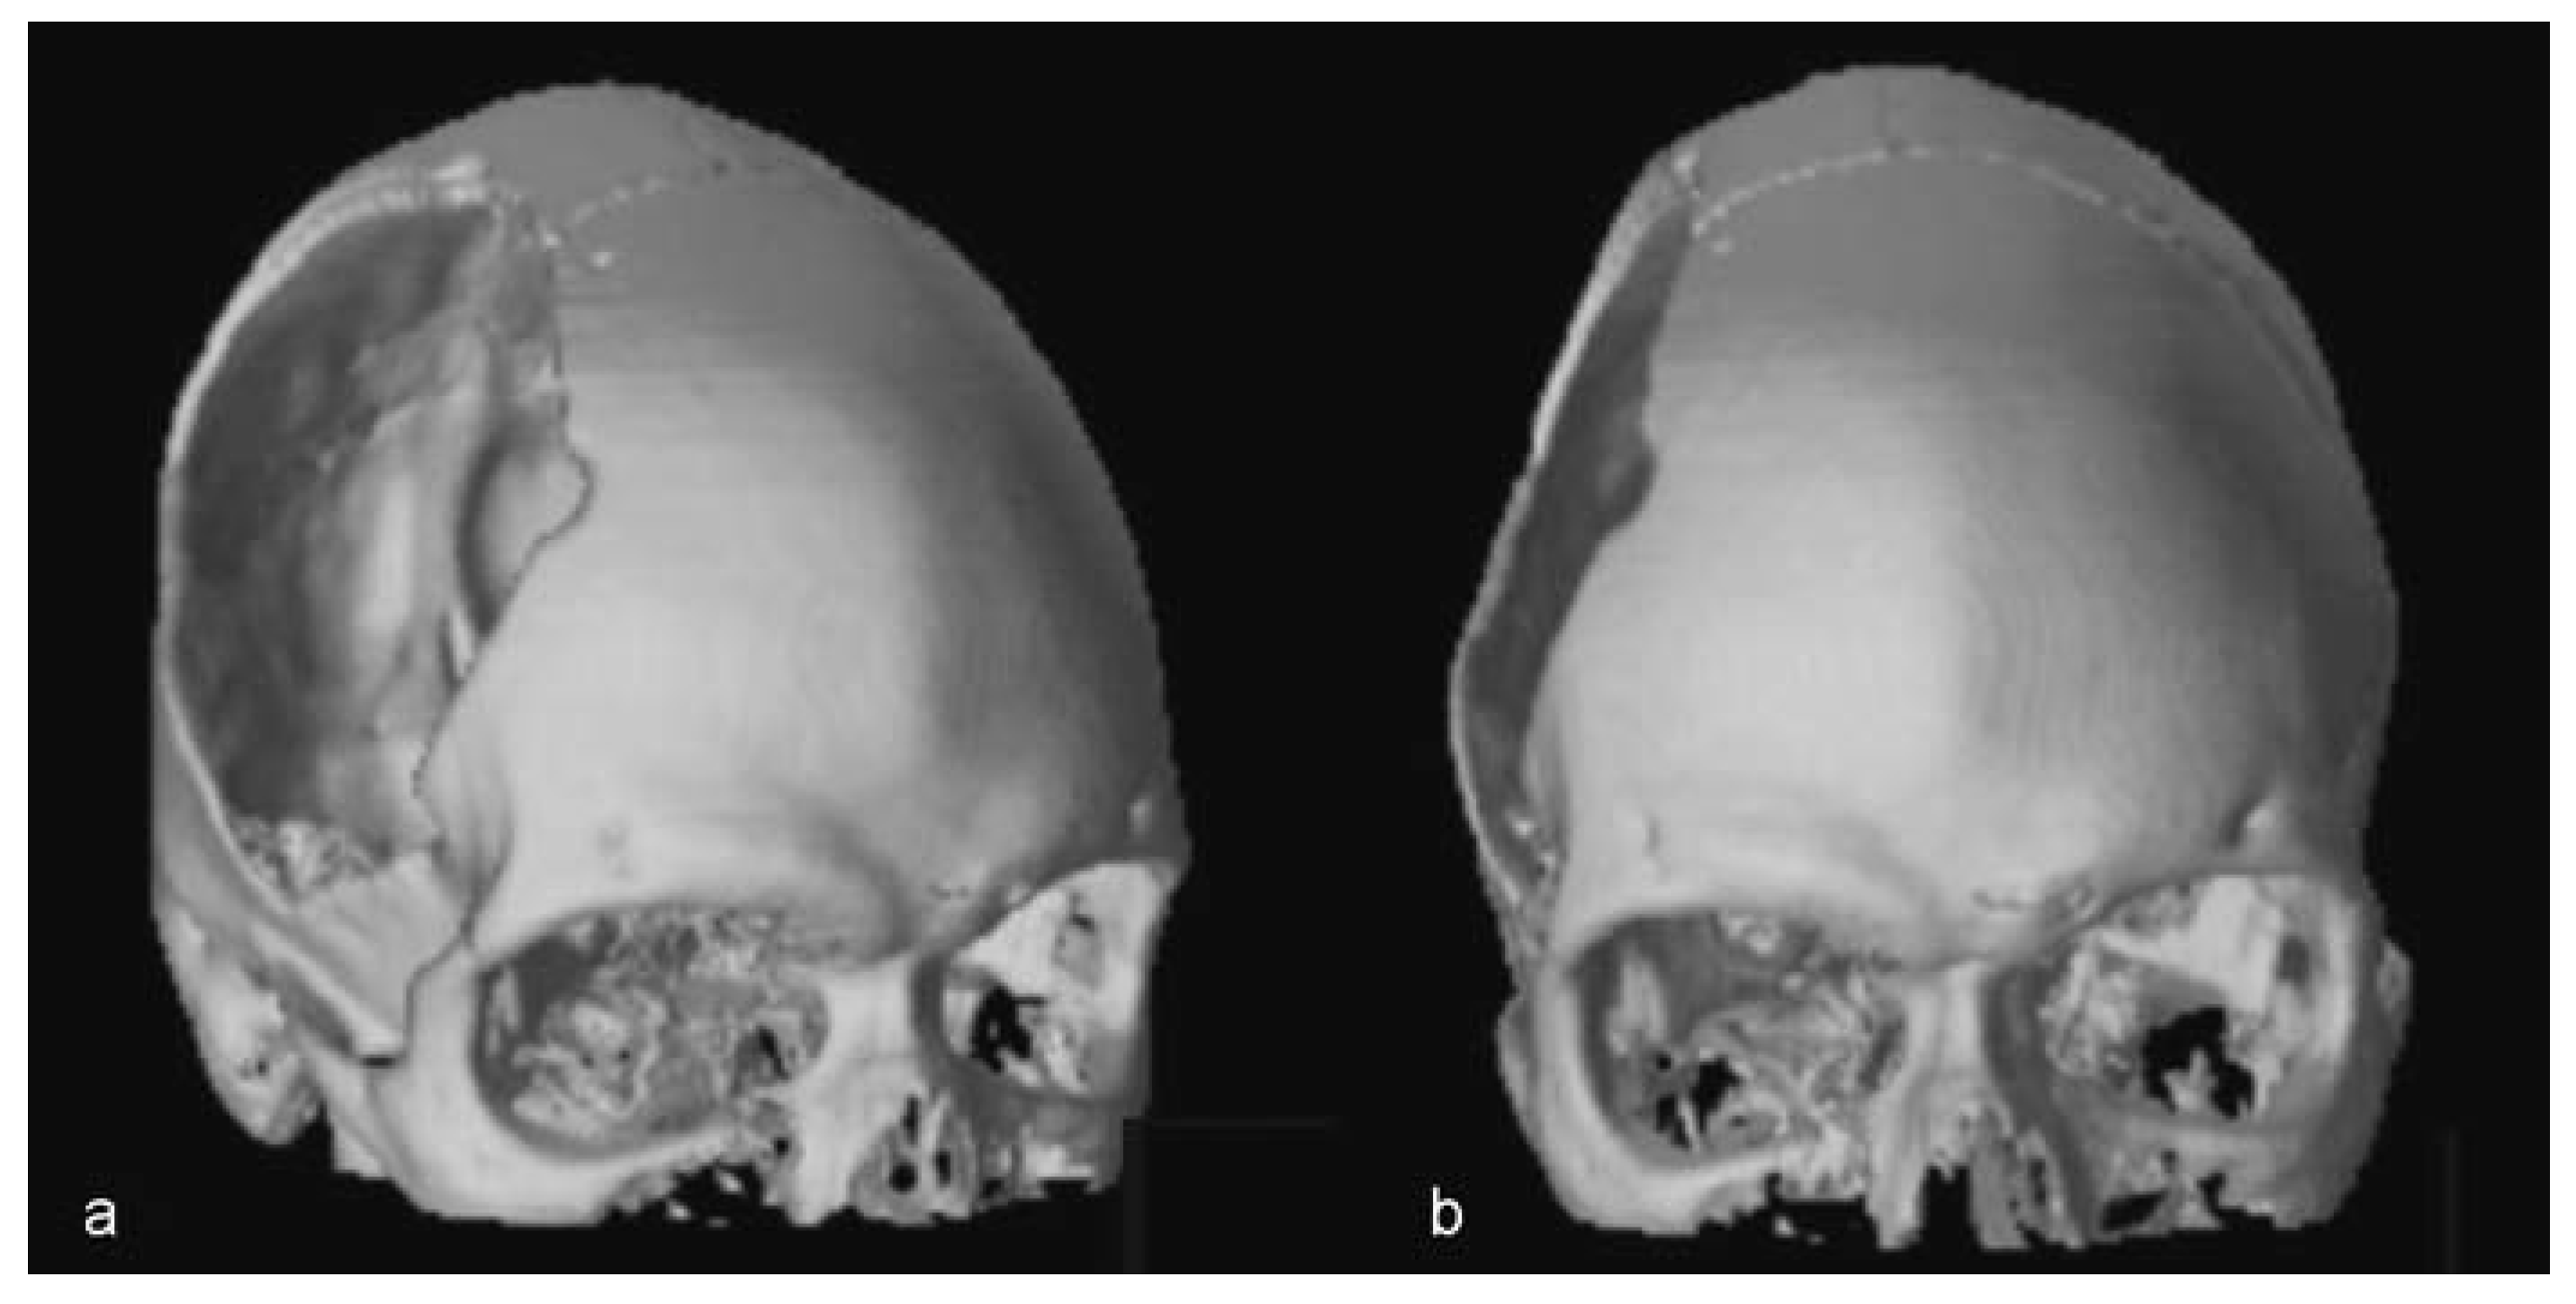

Twenty-eight months after the procedure, the patient was well, with appropriate skull contour reporting no complaints and was very happy with the result (Figure 10 and Figure 11).

Figure 10. (a,b) Postoperative view, after 28 months of temporoparietal reconstruction. The postoperative result showing the correct contour of the cranial vault.